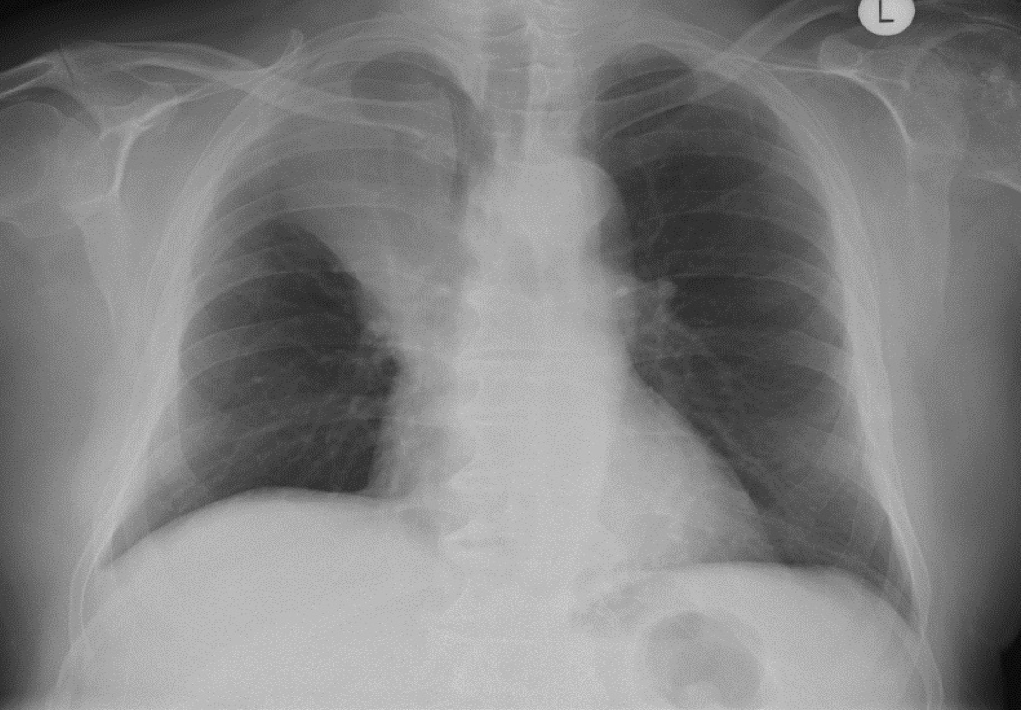

What is this AP CXR showing?

Left Lower Lobe collapse –> Sail sign

Loss of silouette sign of left demidiaphragm and descending aorta

Inferior displacement of left hilum

Inferior displacement of oblique fissue